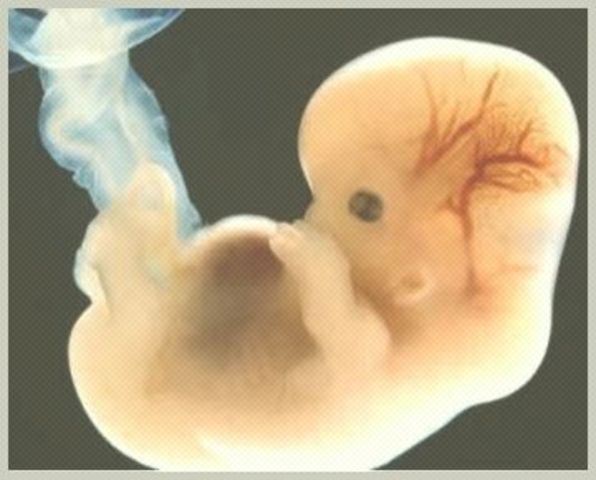

Se desarrolla el embrión,que tiene básicamente una cabeza,un tronco y una cola rizada; empieza a desarrollar los cimientos de lo que serán sus órganos, sus rasgos y su sistema nervioso.

Aparecen dos pequeñas cavidades oculares y la formación de sus orejas y los ojos entran en una fase primaria.

La placenta, que es el órgano que nutrirá al bebé en los próximos nueve meses, también se empieza a formar. Tu volumen de sangre aumenta en un 50%, para afrontar la demanda de oxigeno del feto

El embrión tiene aproximadamente el tamaño de un grano de arroz a las 6 semanas de embarazo. Sus ojos están ahora más separados y la cabeza es enorme en comparación con el cuerpo, supone un tercio del cuerpo entero. Esta desproporción será la tendencia del pequeño incluso en sus primeros años de vida.

Ya tiene párpados,labio superior, nariz y orejas se están empezando a formar. El cuerpo se está alargando, pueden reconocerse lo que serán brazos y piernas, y es posible ver el esqueleto a través de su piel, que es translúcida.El esqueleto está formado por un cartílago suave todavía, no son huesos.

Hasta ahora, el embrión dependía del saco vitelino que, según se cree, le proporciona nutrientes.Entonces cuando la placenta asume la función de alimentarlo a través del cordón umbilical